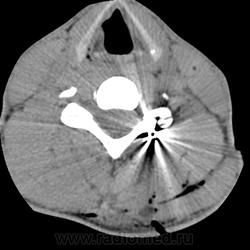

KT С-spine. Огнестрельное проникающее ранение позвоночника. Инородное тело в позвоночном канале на уровне С1 и в мягких тканях на уровне С5, без неврологической симптоматики.

Мужчина 23 года. Получил огнестрельные ранения в области шеи (ружье), стреляли сзади. Неврологическая симптоматика отсутствует. Снаряд прошел по касательной между затылочной костью и атлантом. В желудочковой системе головного мозга кровь. Нейрохирурги пытались удалить инородное тело из позвоночного канала, но тщетно.